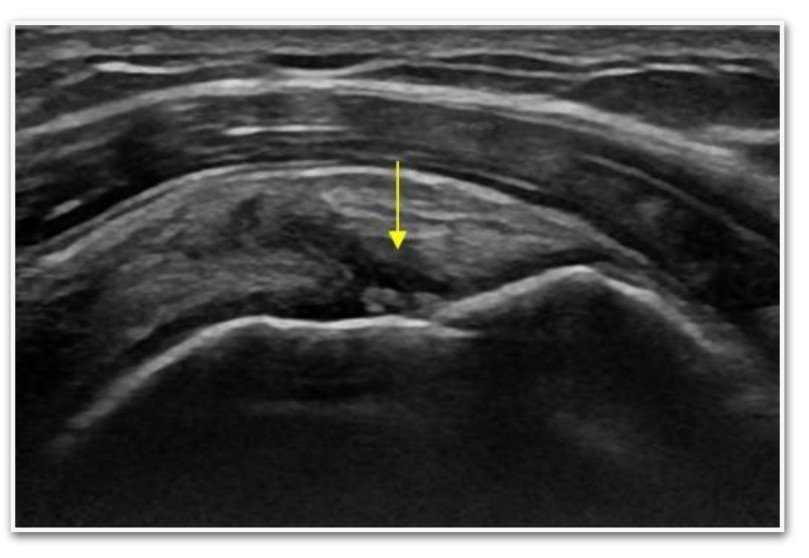

2. Pav. Rotatorių manžetės dalinis plyšimas (echoskopinio tyrimo vaizdas)